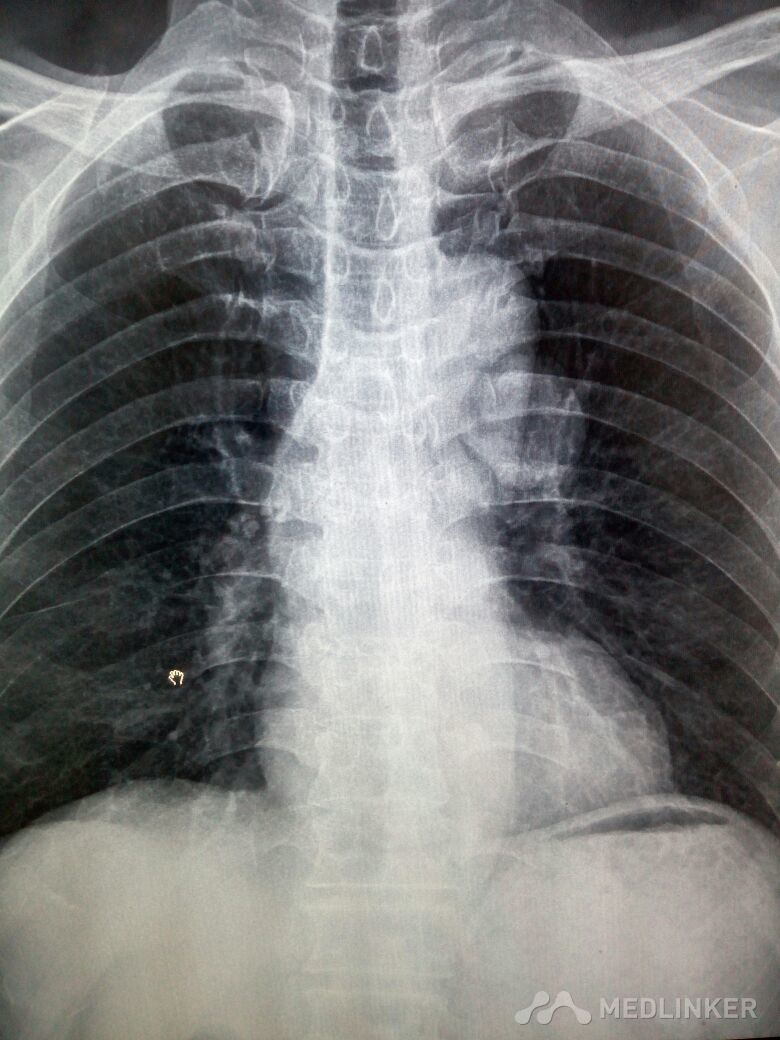

肺内错构瘤一例

患者体检时发现,手术,病理证实错构瘤